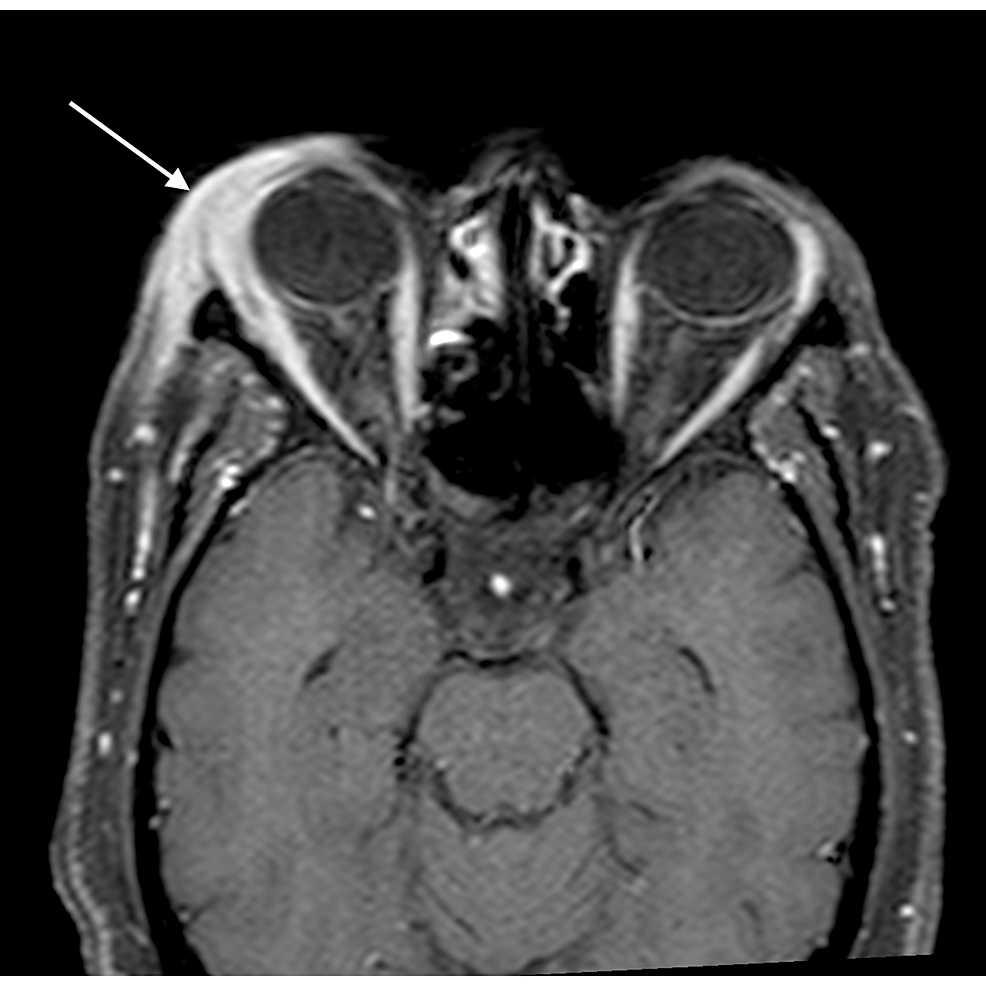

1. An orbital abscess (Figures 5-6);

2. Preseptal cellulitis and abscess (Figures 7-8);

The most common complication of orbital cellulitis was orbital/periorbital abscess formation (eight cases, 53.3%), followed by optic neuritis (four cases, 26.67%), intracranial involvement (four cases, 26.67%), dacryoadenitis (three cases, 20%) and cavernous sinus thrombophlebitis (three cases, 20%).

Out of fifteen cases, three patients had dacryoadenitis, eight had orbital/periorbital abscess, four had optic neuritis/perineuritis, four had intracranial involvement, and two patients had bone destruction. Meningitis was found in all the four patients with intracranial involvement, while one of these also had focal cerebritis. One of these cases had pituitary adenoma as an incidental finding. The complications are illustrated in Table 5.